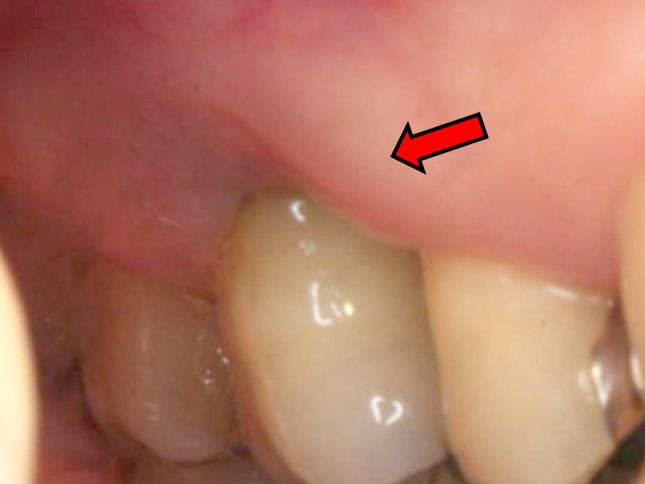

歯周基本治療・歯周外科処置を行なった症例

初診時

歯周基本治療後

初診時年齢:30代女性

治療:歯周病治療

治療法:歯周基本治療、歯周外科処置

治療期間:1年6ヶ月

費用:保険診療

リスク・副作用:歯周外科処置後に出血、腫れ、あざが出ることがありますが時間とともに治ります。術後3週間程度噛んだときの痛みや歯が浮いた感じがすることがあります。術後の歯肉退縮により知覚過敏が生じることがあります、時間とともに落ち着くこともありますが症状が続く場合は根管治療を行います。